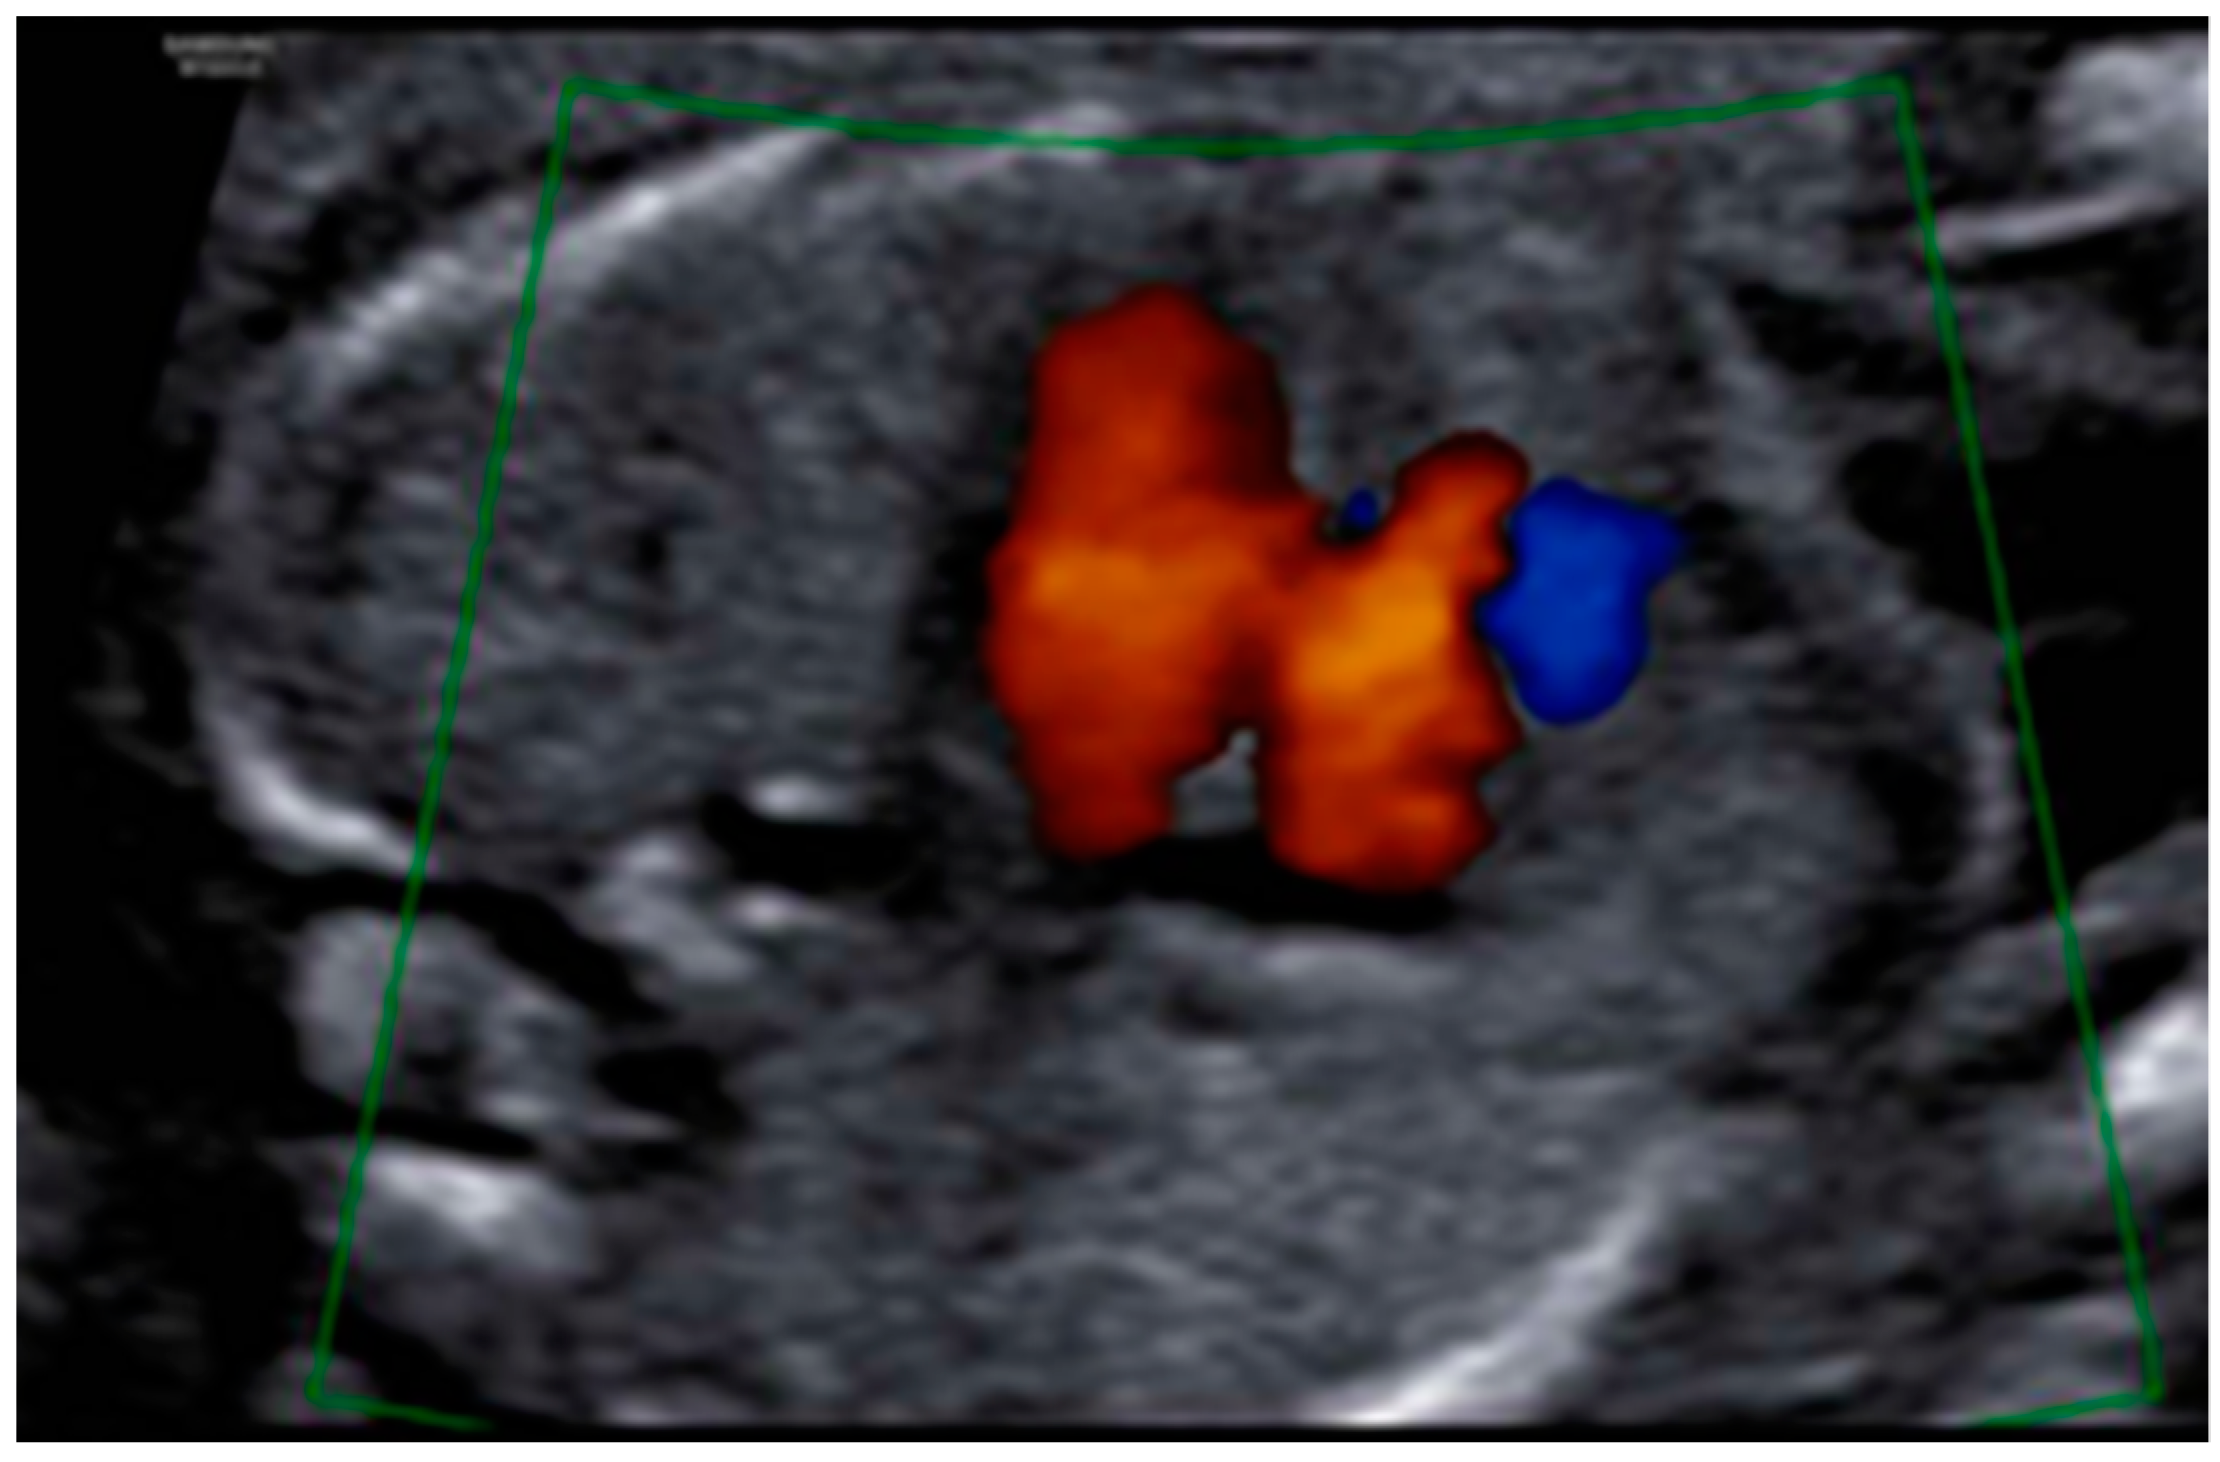

3. Results: Case Presentation